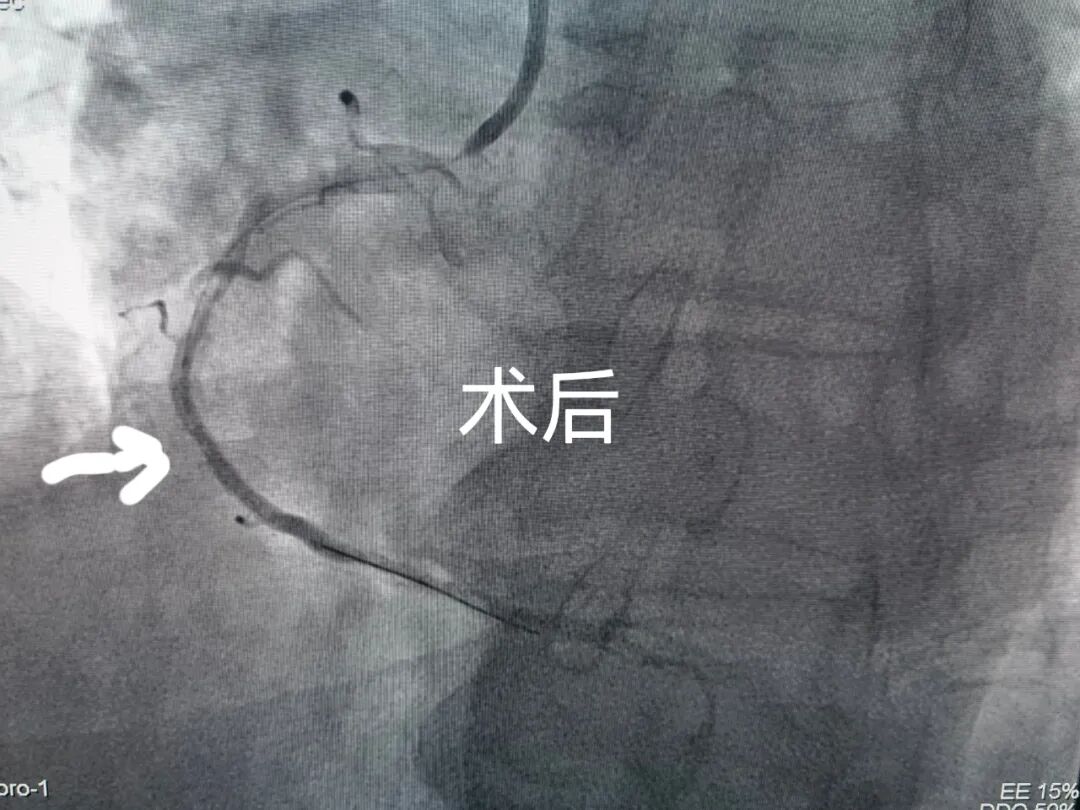

在介入專家張利剛主任醫(yī)師的帶領(lǐng)下,目前能獨(dú)立進(jìn)行急診冠狀動脈造影及冠狀動脈內(nèi)支架植入及臨時起搏器安裝術(shù)。邀請北京等地著名專家指導(dǎo)下行永久起搏器植入術(shù)、復(fù)雜性心律失常射頻消融術(shù)、先天性心臟病的介入治療。開辟了急性心肌梗死綠色通道,保證了全年24小時急診醫(yī)護(hù)人員隨時到位。每年獨(dú)立完成冠狀動脈造影200余例,冠狀動脈支架植入80余例。